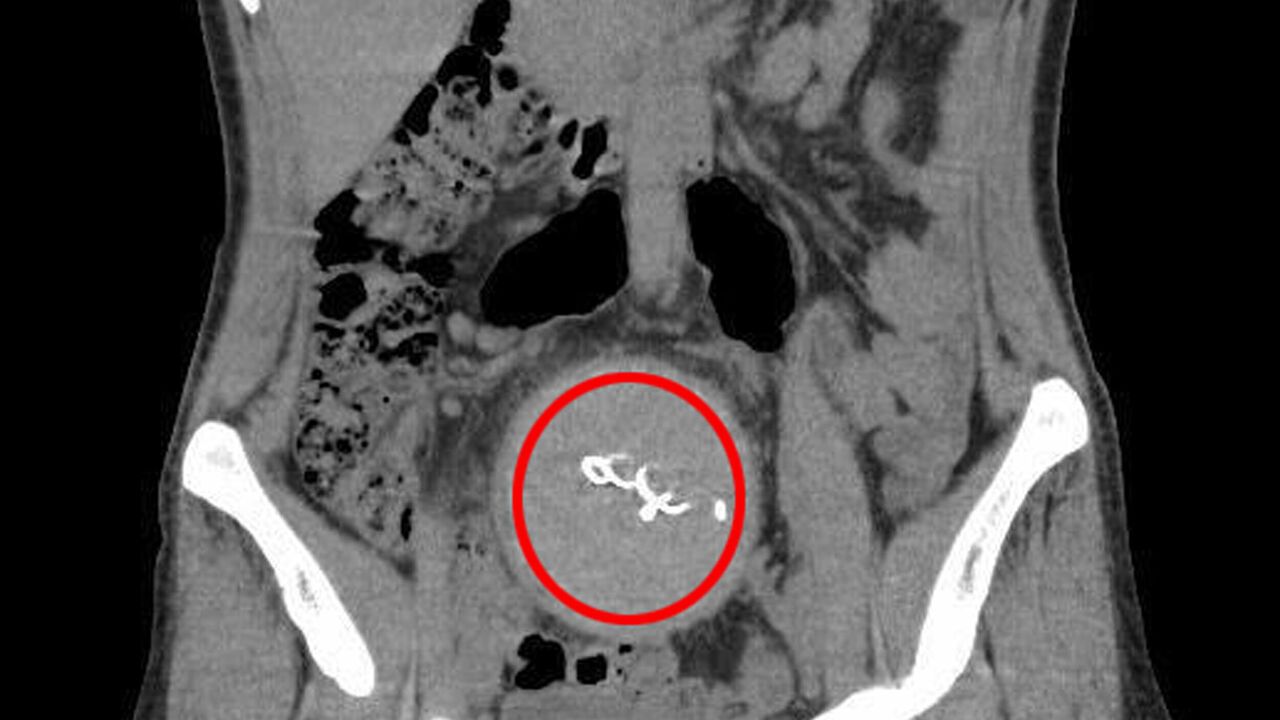

Burada yapılan kontrolde, doktor acil tomografi çektirmesini istedi. 2023 yılının Ağustos ayında çekilen tomografide, Y.S.'nin vücudunda doğum sonrası unutulan sargı bezi görüldü. Şoke olan Y.S., 2 yıldır yaşadığı ağrılara ihmalin sebep olduğunu öğrendi. Y.S.'nin karnında unutulan yaklaşık 30 santimetre uzunluğundaki gazlı bez ameliyatla alındı. Y.S., hastane ve süreç içerisinde ihmali bulunan doktorlar hakkında savcılığa suç duyurusunda bulundu.

Doktor E.B. ifadesinin devamında şöyle dedi: "İnceleme alanıma girdiği kadarıyla batındaki bağırsak anslarında ileri derecede distansiyon (karın şişliği) olduğundan bahsedilmiştir. Yapılan ikinci gözlemde de bağırsaklarda geçiş tıkanıklığı tanısı konulmuştur. Benim gerçekleştirdiğim işlemde herhangi bir eksik ve atlama yoktur. Aksine Gossypiboma (hastanın vücudunda yabancı cisim unutulması) varlığında erken dönemde görülebilecek en olası patolojik durum olan tıkanıklık tanısı konulmuştur. Bundan sonrası klinisyenin değerlendirmesiyle sonuçlandırılabilecek bir süreçtir. Kullanılan gazlı bezin radyopak madde ile işaretli olmaması da tanısal gecikmede rol oynamıştır."